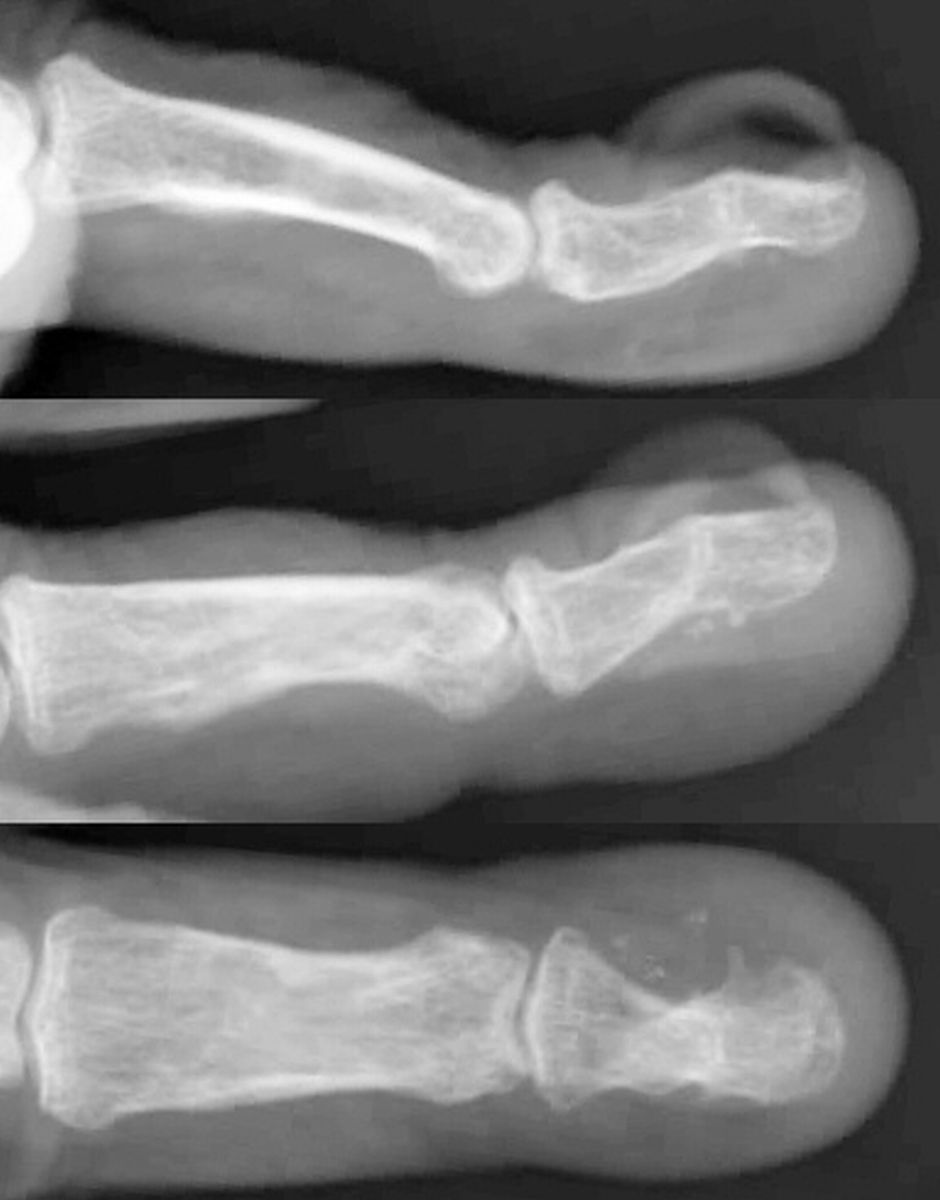

Clinical Examples: Nailbed Ablation and Skin Graft

The fingernail complex is ...complex. Local flaps are unavailable for resurfacing large nail bed defects, and regional or pedicled flaps are not justified in most situations. Fortunately, the dorsal cortical bone of the distal phalanx provides a well vascularized stable bed for a skin graft. These three cases illustrate the use of full thickness skin grafts for nailbed defects following nailbed ablation.

Case 2.

Nuisance posttraumatic deformity.

Defect following sterile and germinal matrix excision with periosteum, dorsal cortex exposed. This was resurfaced with a small full thickness skin graft from the proximal medial forearm (not shown).

Three months postop.